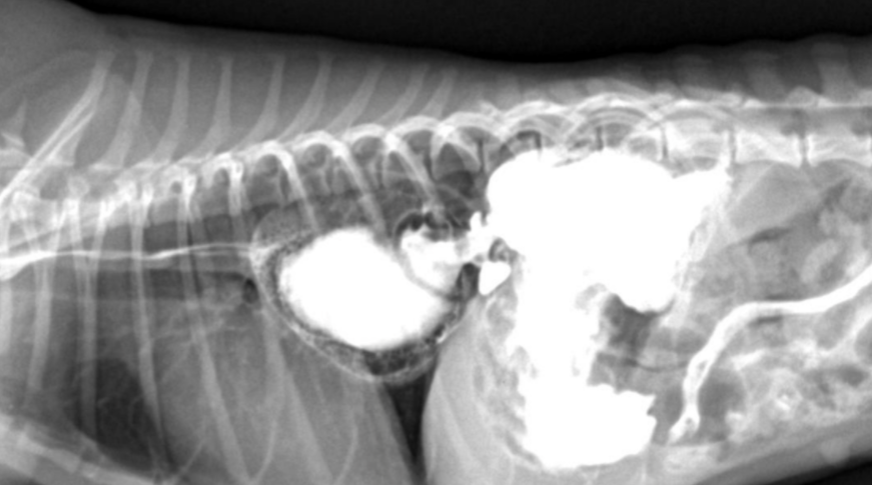

์ํ์ฅ : GD vs. GDV

- ๊ฐ๋ณ์ key point๋ pylorus์ ์์น & ์์ ๋ถํํ(compartmentalization) !

- ์ ์์ ์ธ ์์น๋ ์ธ์ธก์์์ ์๋์ชฝ, ๋ณต๋ฐฐ์์์ ์ผ์ชฝ์ ์์น.

- GD๋ ์๊ฐ ํ์ฅ๋์ด ์์ผ๋, ์์น๋ ๊ทธ๋๋ก.

- GDV๋ ์ฅ์ด ๊ผฌ์ด๋ฉด์ ์์น๊ฐ ๋ฌ๋ผ์ง๋ฏ๋ก, pylorus์ ์์น๊ฐ ์ธ์ธก์์์ ์์ชฝ

| GD | GDV | |

|---|---|---|

| VD | - greater curvature ์ผ์ชฝ(์ ์) * 360๋ ํ์ ์์๋ ์ผ์ชฝ์ ์์น | - greater curvature ์ค๋ฅธ์ชฝ (180๋ ์ผ์ ) - duodenum ์์น๋ ํจ๊ป ๊ผฌ์ |

| RL | - pylorus๊ฐ ์๋์ชฝ(์ ์) | - pylorus ์์ชฝ - ์์ ๋ถํํ(compartmentalization) : ๋ถ๋ฐฉ ํ์ธ - gastric band (soft tissue) ๊ด์ฐฐ |

![]() ![]() | ![]() ![]() | |

[๋ถํํ]![]() ![]() |